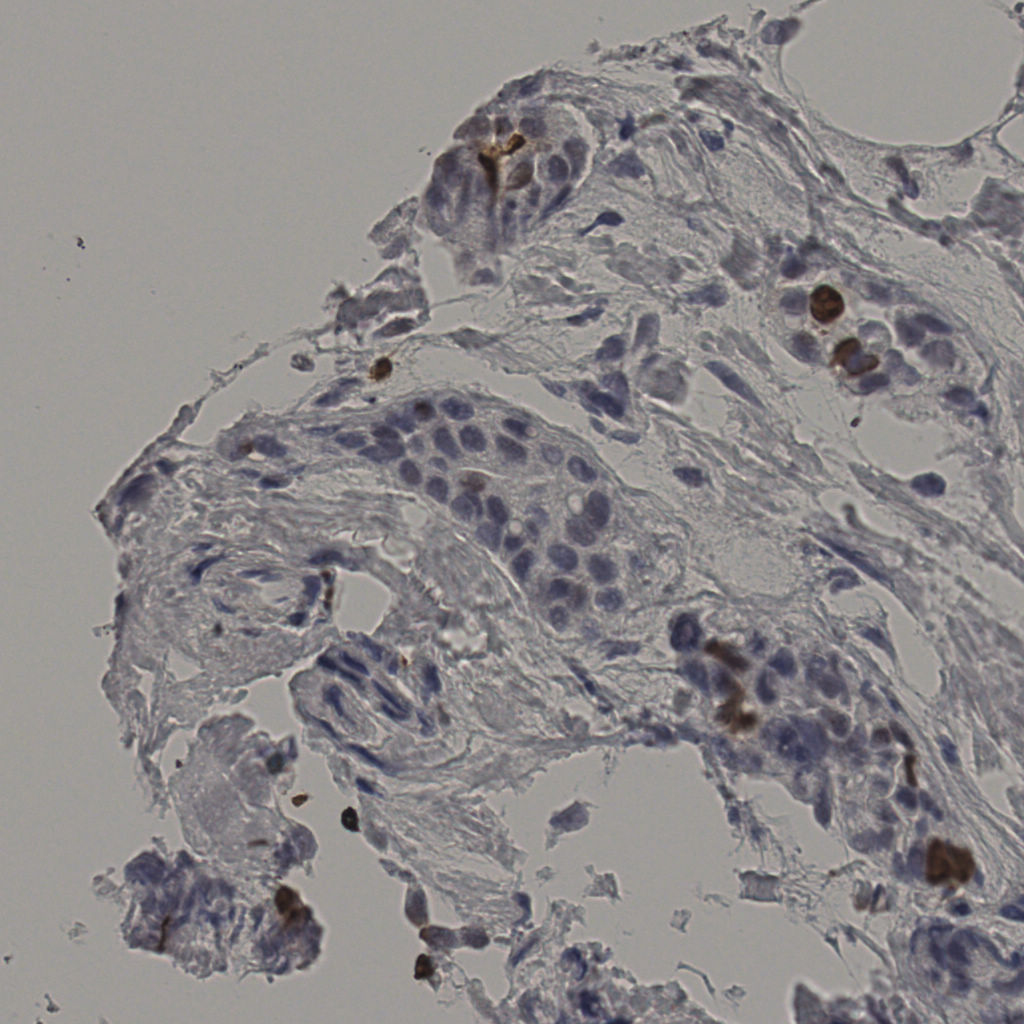

缩略图

标记后

标记前